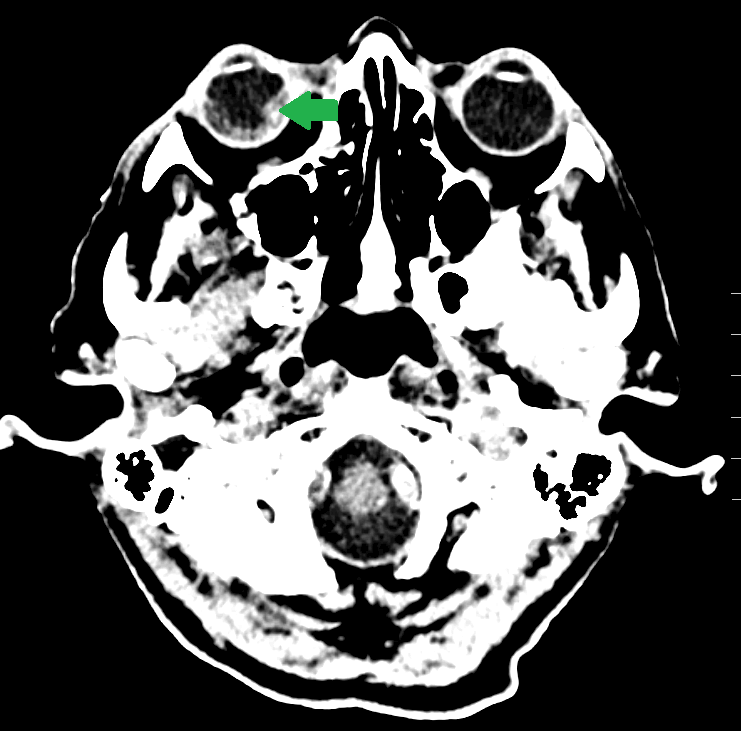

A dramatic head CT in a patient with monocular vision loss.

An elderly woman presented to the ER with complaints of sudden right sided headache and monocular right eye vision loss. Her blood pressure on presentation was 240/110 mmHg. Her non-enhanced head CT is shown.

In this case, the patient had a retinal hemorrhage in the right eye.